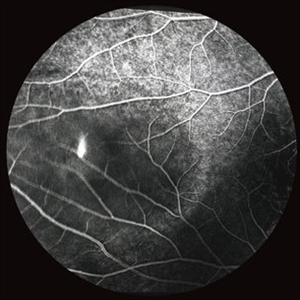

Central Serous Chorioretinopathy with Smokestack Late Phase

CSCR with smokestack, late phase.

Condition/keywords: central serous chorioretinopathy (CSCR), late phase, smokestack